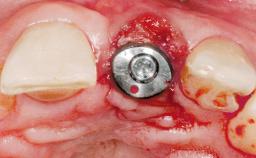

Late Placement of an Implant in a Maxillary Left Central Incisor Site

Type of Implants Two-Piece

Attachment Two-Piece

Abutment Type Customized

Prosthesis Type FDP